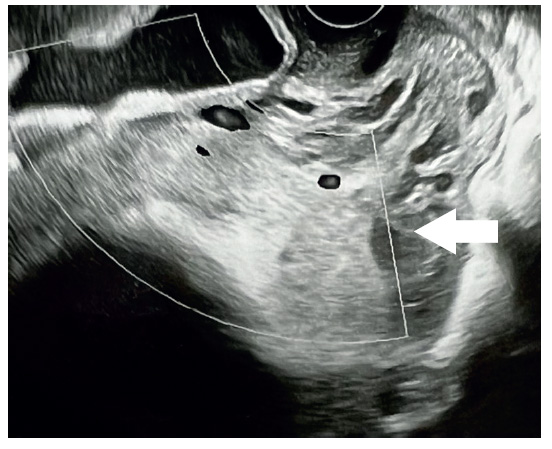

Figura 4.Lagunas placentarias ovaladas irregulares.

En la valoración ecográfica (tabla 2), la pérdida de la zona clara de la inserción placentaria para pacientes con sospecha de acretismo fue de 41,7%, había lagunas placentarias ovaladas no circulares de bordes irregulares en 75,0%, interrupción de la pared vesical en 50,0%, heterogeneidad e hiperecogenicidad placentaria en 66,7%, placa corial de aspecto despulido, hiperecogénica e irregular en 75%, hipervascularización uterovesical en 58,3%, hipervascularización subplacentaria en 50,0%, vasos nutricionales y lagunas placentarias hipervascularizadas en 66,7%, hipervasculatura intraplacentaria en 50%, y velocidad máxima de flujo de 52,3 cm/seg.

El análisis estadístico mostró que la pérdida de la zona clara, las lagunas placentarias ovaladas no circulares de bordes irregulares, la interrupción de la pared vesical, la hiperecogenicidad y heterogeneidad placentaria, la placa corial de aspecto despulido, hiperecogénica e irregular, la hipervascularización útero vesical así como la hipervascularización subplacentaria, vasos nutricionales e hipervascularización intraplacentaria presentaron relación estadísticamente significativa con el acretismo placentario (p<0,05). Y laflujometría representada por la velocidad máxima encontrada en el estudio Doppler con barrido de toda la placenta fue 52,3 para acretismo frente a 26,0 en placentas previas sin signos de acretismo, diferencia que fue estadísticamente significativa (p<0,05).

Los hallazgos ecográficos más llamativos son la localización anormal de la placenta, hiperecogenicidad y heterogeneidad a la escala de grises en diversas zonas placentarias, parénquima placentario muy diferente al que estamos acostumbrados cuando observamos placentas normoinsertas 17). Por otro lado, se puede evidenciar modificaciones anatómicas de la placa basal y de la placa corial en la ecografía, producto de un proceso neoproliferativo que afecta toda la placenta en forma focal, parcial o total 18). Y la sombra que la acompaña es la presencia de lagunas vasculares de bordes irregulares, que no solamente tienen manifestaciones en la escala de grises sino, más bien, en el flujo aumentado en la placenta al medir con la flujometría Doppler. Estos hallazgos son sugerentes de acretismo 18,19).